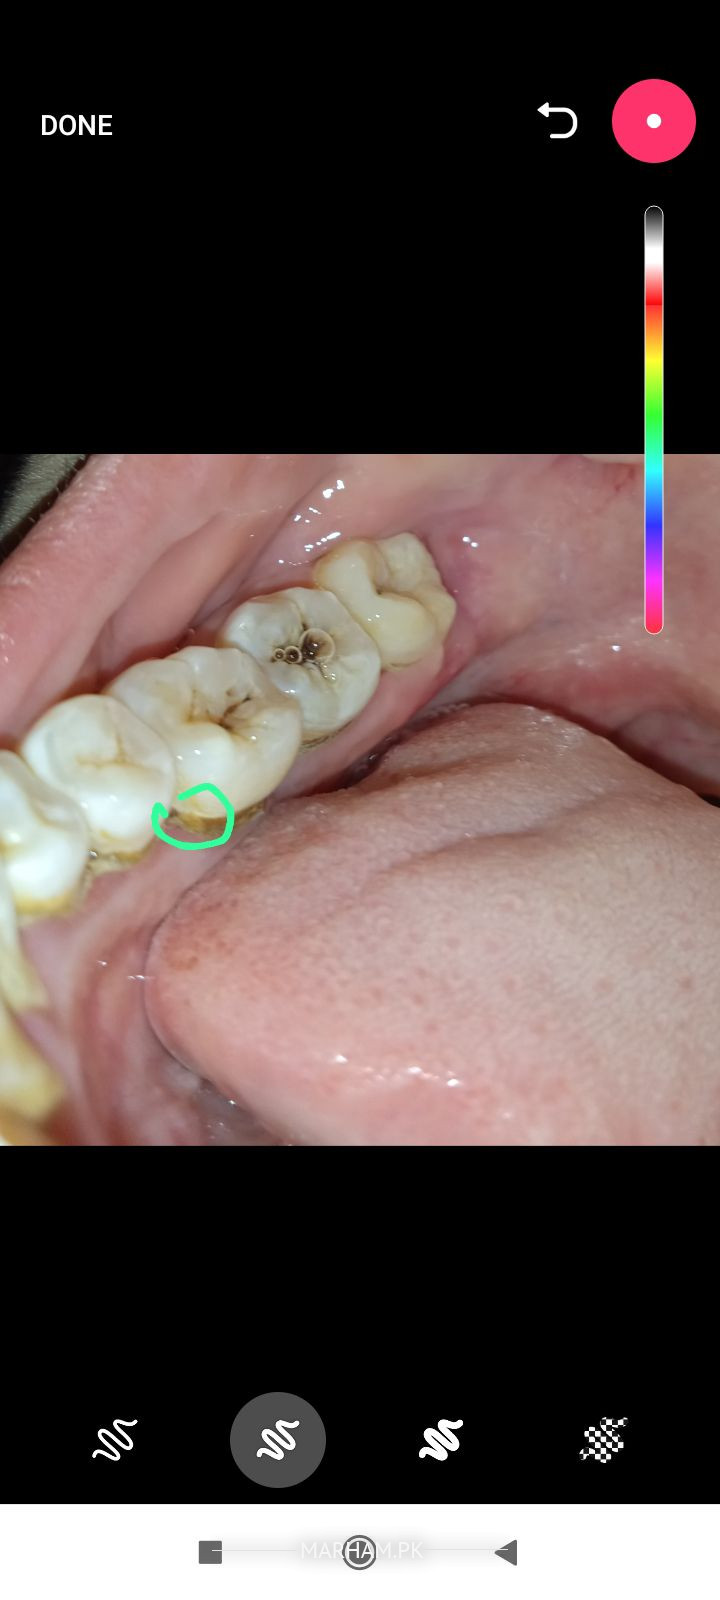

میرے دو دانتوں کے درمیان جڑوں میں ہلکا سا سوراخ ہے۔۔ تین چار دن سے ایسا ہو رہا ہے جب میں لیٹتی ہوں درد شروع ہو جاتا ہے۔۔ میری پریگننسی کا دوسرا منتھ ہے ۔۔ کاہنڈلی کوئی دوائی تجویز کر دیں ۔۔ جس سے پریگننسی کو نقصان نا ہو ۔۔اور درد بھی ٹھیک ہو جائے ۔۔اوپر تصویر میں نے نشان دہی کی ہے جگہ کی

apko scaling krwani chahye. dentist ko check krwaen. ho skta ha filling ki zrurat ho. akhri se agly dant ma keera lga ha.. scaling r filling pregnancy ma ho skti ha.

Apk sath waly or is daant ma keera laga hua h jiska waqt pa ilaaj krna zaroori h wrna ksi b wqt shadeed dard ka samna krna par skta h. Mera mashwra h ap appointment lylain or clinic ma a k treatment krwa lain.